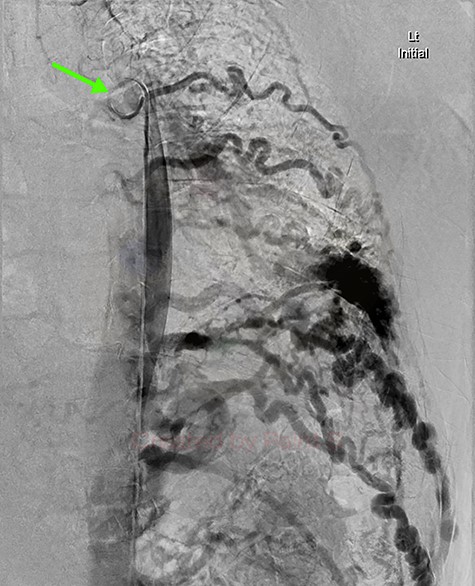

Aortic DSA using a pigtail catheter (green arrow), demonstrating extensive arterial collateralization between the left chest-wall intercostal arteries and the left lower lobe PAVM.

Given the findings, he was referred to Interventional Radiology for a formal digital subtraction angiogram with view of transcatheter embolization. Under local anaesthetic and sedation, a 5-french sheath was placed in the left common femoral artery. Using a 5-french pigtail catheter, aortic angiography was undertaken, confirming the CTPA findings and demonstrating predominant supply of the vascular malformation via the left intercostal arteries and the left inferior phrenic artery (Fig. 4)—draining into the left inferior pulmonary artery and vein. Superselective catheterization of the left intercostal arteries (Fig. 5) and the left inferior phrenic artery (Fig. 6) are shown. Unfortunately, due to the malformation’s volume and complexity, embolization was abandoned. He was subsequently referred to Cardiothoracic Surgery, currently awaiting consideration and workup for ligation and resection via video-assisted thoracoscopy, and potentially thoracotomy.